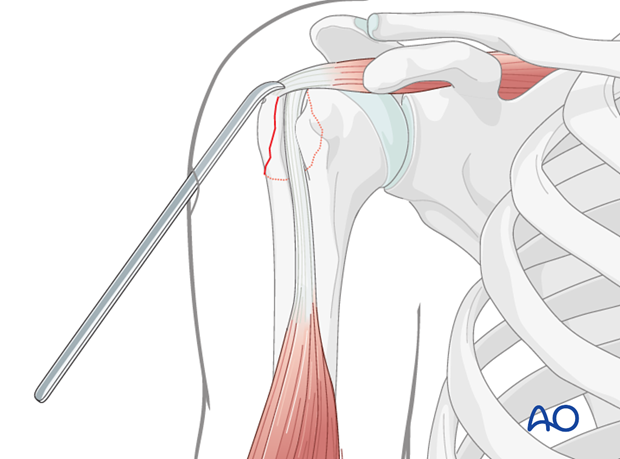

This image likely illustrates the initial exposure of the fracture site via the deltopectoral approach, revealing the displaced greater tuberosity fragment.

* Using bone hooks or K-wires as joysticks, the GT fragment is carefully manipulated. The fragment typically needs to be pulled inferiorly and anteriorly to counteract the rotator cuff pull.

* Reduction clamps (e.g., pointed reduction forceps, Verbrugge clamp) can be applied carefully to compress the GT fragment back onto the humeral head.

* Temporary K-wire fixation can be used to maintain reduction while definitive screw fixation is planned and applied.

This image illustrates the use of a reduction instrument, likely a pointed reduction forceps, to manipulate and hold the greater tuberosity fragment in its anatomical position prior to definitive fixation.